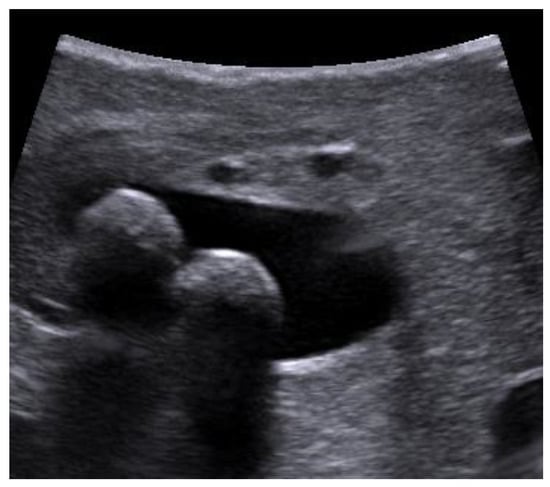

The distal part of the common bile duct (retro-duodenal and intra-pancreatic) and the area of the papilla Vateri were scanned through the duodenum. The left and right hepatic ducts and their junction were investigated through the right hepatic lobe. The main metrics examined in the study were the maximum width of the bile duct, its content (gallstones), the maximum size and the quantity of the stones. Stones were considered as a positive finding on LUS or choledocholithiasis (Figure 2), as well as biliary sludge in the lumen of the bile duct.

Figure 2. Stones in the bile duct (photo by the author).